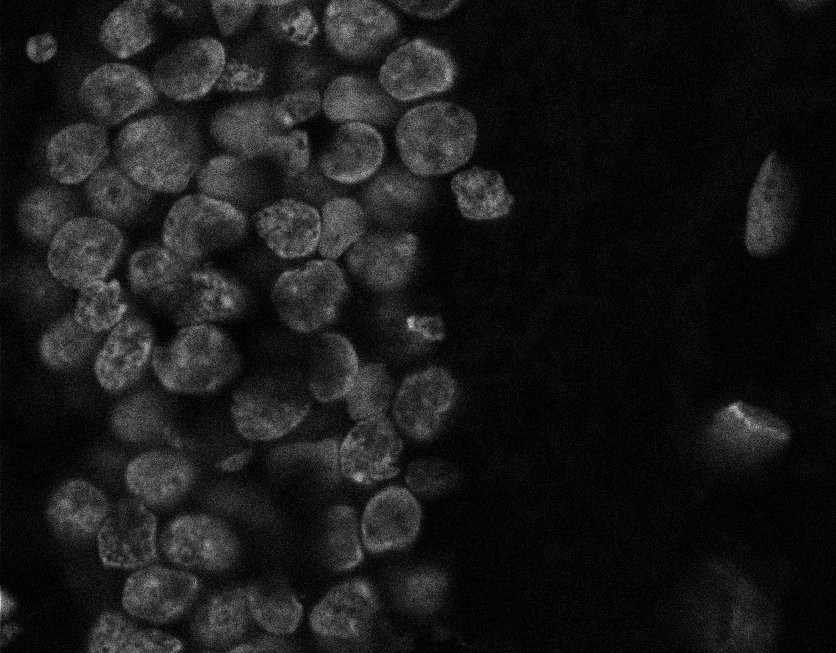

Nuclei

Nuclei - Bis